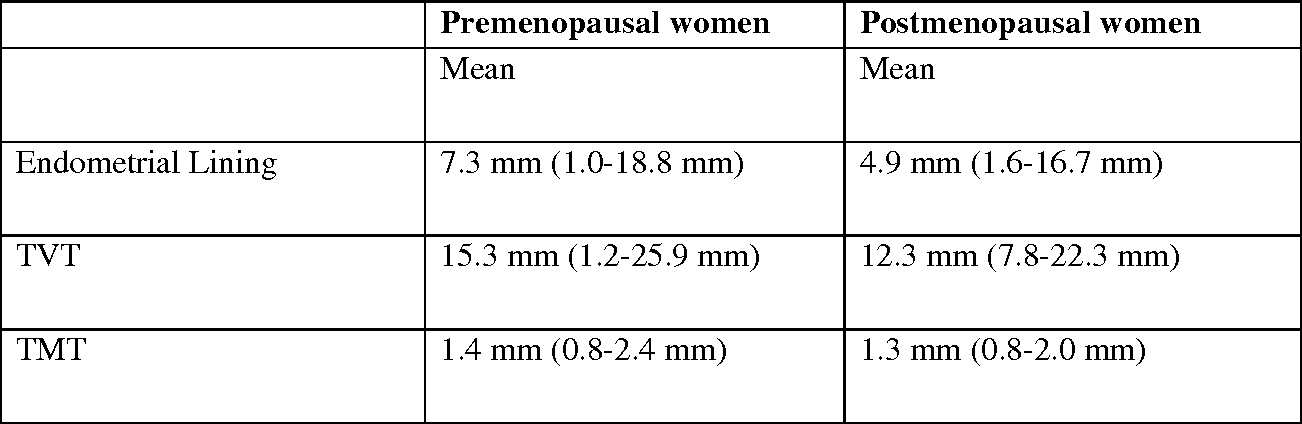

Table 2 From Assessing The Thickness Of The Vaginal Wall And .

Endometrial Thickness What Is Normal And How To Measure .

Endometrial Thickness Radiology Reference Article .

Endometrial Thickness An Overview Sciencedirect Topics .

Sonohysterographic Measurement Of Endometrial Thickness .